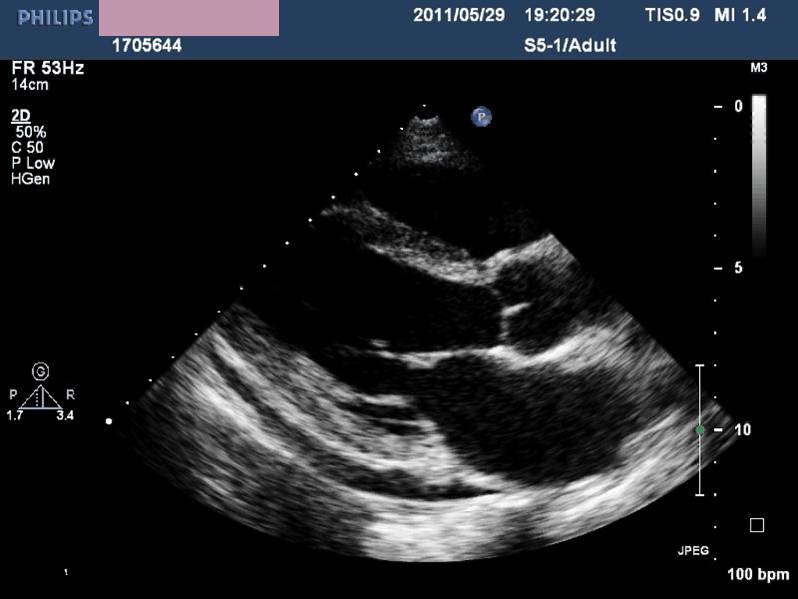

——各房室内径正常,左室收缩功能及室壁运动未见异常,LVEF 72%,少量心包积液(入院后1周)。

诊治经过-第二次心脏超声

◆一周内完全恢复

——病毒性心肌炎?

应激性心肌病?

——根据随诊表现,患者最终诊为应激性心肌病